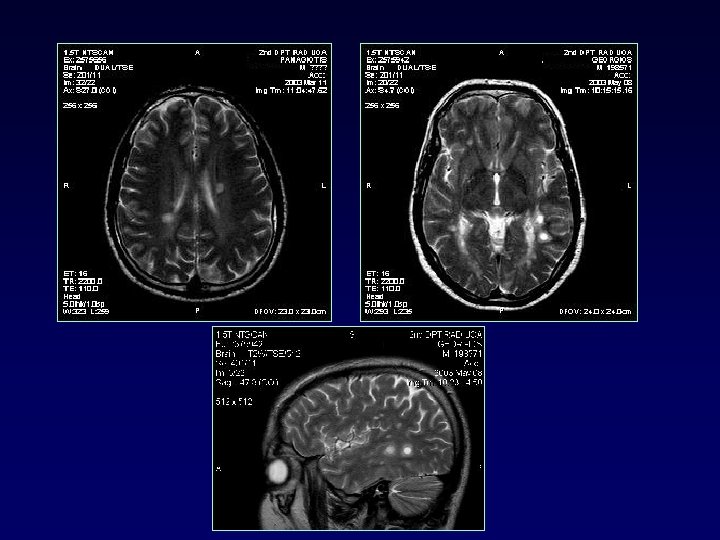

Lesions indicative MS • Brain stem, subcortical, spinal cord • Posterolateral pons, cerebelar peduncles • Enhancement MS vs small vessel

Combine MRI brain+spinal cord BRAIN CVD 17 CONNECTIVE TD 18 SLE 13 SJOGREN 7 SARCOID 5 INTERMED UVEITIS 6 MS(25) O. Ν. D(66) CORD 100% 92% 65% 6% “In contrast to MS, cord lesions are very uncommon in OND. This finding can help differentiate these disorders” Bot J. C. , Barkhof F. et al Differentiation of Multiple Sclerosis from Other Inflammatory Disorders and Cerebrovascular Disease: Value of Spinal MR Imaging Radiology 2002 223: 46 -56;